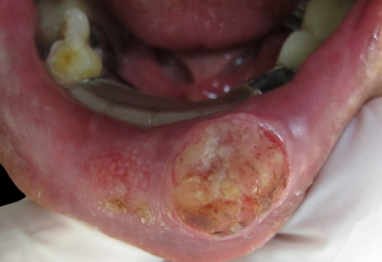

鱗狀細胞癌 (Squamous Cell Carcinoma)

這是第二常見的皮膚癌,比基底細胞癌更容易擴散及侵犯周圍的組織,但也相對比較少見。它可能表現為紅色、鱗狀的斑塊,或是一個結痂、粗糙的腫塊。